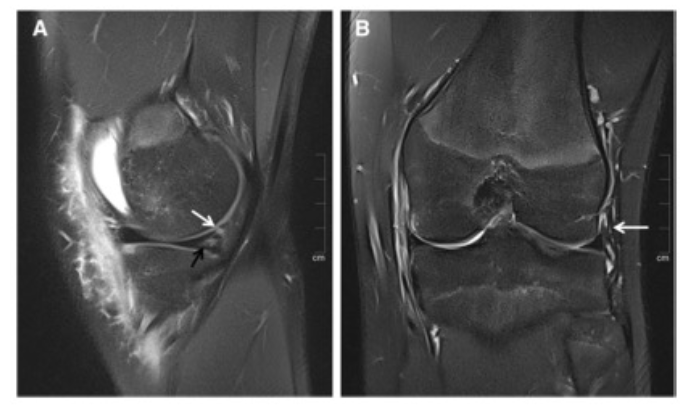

图 19岁男性急性前交叉韧带撕裂(未显示)。A 矢状面,质子加权脂肪抑制TSE序列显示1型斜坡病变,周边有垂直撕裂的半月板帽韧带(白色箭头)。在PHMM中,显示了一个相关的实体内撕裂(黑色箭头)。B 冠状位,质子加权脂肪抑制的TSE序列显示一个正常的ALL,没有损伤的迹象(箭头)